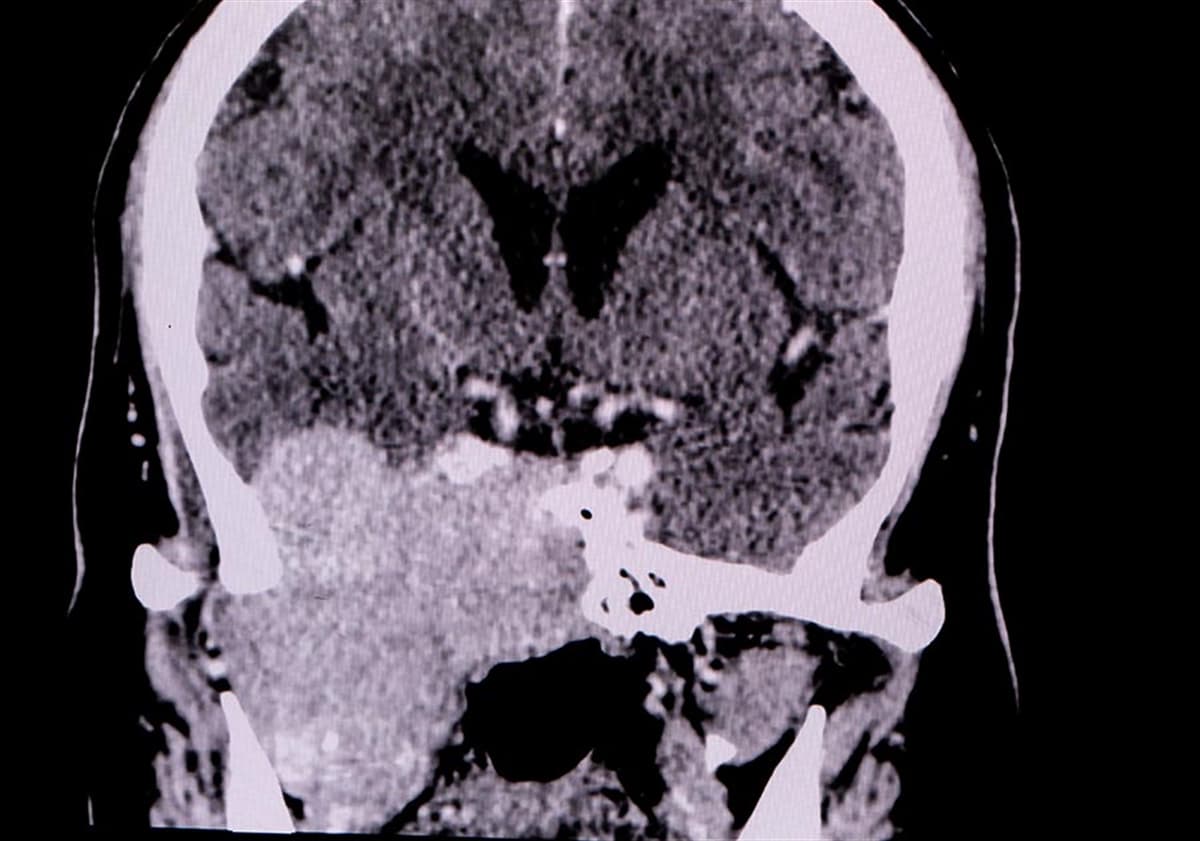

- MR ve BT: Manyetik Rezonans (MR) VE bilgisayarlı tomografi (BT) kafa tabanı tümörünün teşhisinde önemli rol oynayan görüntüleme yöntemleridir. Bu yöntemler, hem kafa tabanı tümörü hem de diğer beyin tümörlerinin belirlenmesinde sıklıkla başvurulan teşhis araçlarıdır.